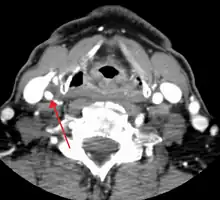

One of several different imaging modalities, such as a computed tomography angiogram (CTA)[12][13][14] or magnetic resonance angiogram (MRA) may be useful. Each imaging modality has its advantages and disadvantages - Magnetic resonance angiography and CT angiography with contrast is contraindicated in patients with chronic kidney disease, catheter angiography has a 0.5% to 1.0% risk of stroke, MI, arterial injury or retroperitoneal bleeding. The investigation chosen will depend on the clinical question and the imaging expertise, experience and equipment available.[15]